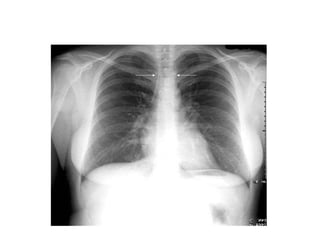

This document provides an overview of interpreting chest x-rays and identifies several key factors. It discusses the importance of inspiration, penetration, and rotation in obtaining a technically quality radiograph. It also outlines different views of chest x-rays including PA, AP, and lateral views. Finally, it identifies several anatomical structures that should be evaluated when interpreting a chest x-ray such as the lungs, heart, diaphragm, bones, and soft tissues.